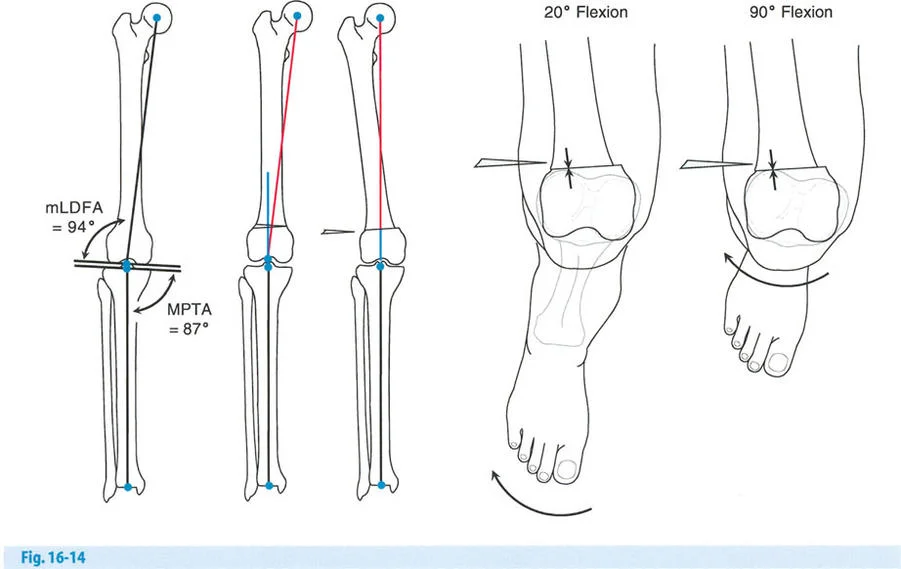

تتمثل الفكرة الأساسية في تغيير زاوية عظم الساق (الظنبوب) أو عظم الفخذ (أحيانًا)، لإعادة توزيع الحمل على مفصل الركبة.

- في حالات التقوس (Varus deformity): حيث يكون الحمل زائدًا على الحجرة الإنسية (الداخلية)، يتم إجراء قطع العظم لتحويل الساق إلى وضعية الروح (Valgus)، مما ينقل الحمل إلى الحجرة الوحشية (الخارجية) السليمة.

- تخفيف الحمل: في الركبة الطبيعية، تتحمل الحجرة الإنسية حوالي 75% من الحمل أثناء الوقوف على ساق واحدة. مع 6 درجات فقط من التقوس الميكانيكي، يمكن أن يصل الحمل إلى 95%. تهدف الجراحة إلى تقليل هذا الحمل إلى حوالي 50% أو أقل.

- تأثير على الرضفة (صابونة الركبة): يمكن أن يؤدي قطع العظم فوق الحدبة الظنبوبية إلى تغير في مستوى الرضفة (Pseudo-patella alta أو Pseudo-patella baja)، مما قد يؤثر على حركة الركبة أو يجعل استبدال المفصل لاحقًا أكثر صعوبة.

- تنبيه سريري: يعيد سمك الطرف الاصطناعي الظنبوبي مستوى الحدبة الظنبوبية، مما قد يسحب الرضفة إلى الأسفل. هذا يمكن أن يعيق ثني الركبة. يولي الدكتور هطيف اهتمامًا خاصًا لهذه التفاصيل لتجنب المضاعفات.